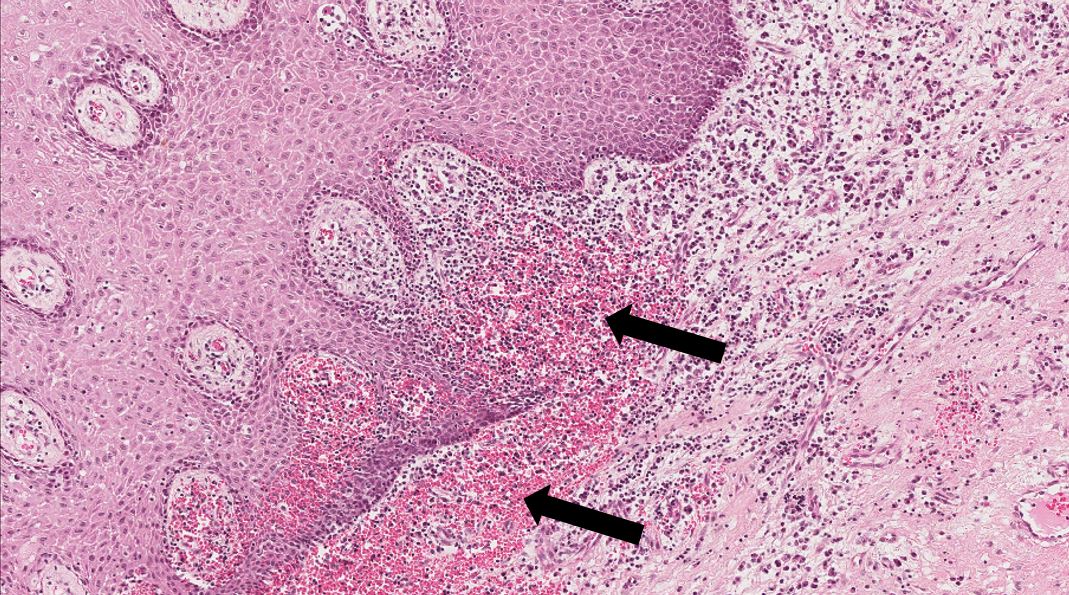

Fragmento de mucosa bucal revestida por epitélio estratificado pavimentoso ceratinizado. No tecido conjuntivo subjacente observa-se intenso edema inflamatório (setas) que se caracteriza por líquido claro contendo proteínas (material amorfo eosinofílico) e células inflamatórias. Notar que o edema (setas) está separando as fibras do tecido conjuntivo. Pode-se observar também aumento do número de vasos funcionantes (hiperemia) e áreas focais de hemorragia.

Acúmulo de líquido rico em células inflamatórias no interstício (fora dos vasos) separando as fibras do tecido conjuntivo. Nas fotos abaixo está ilustrado o edema inflamatório.